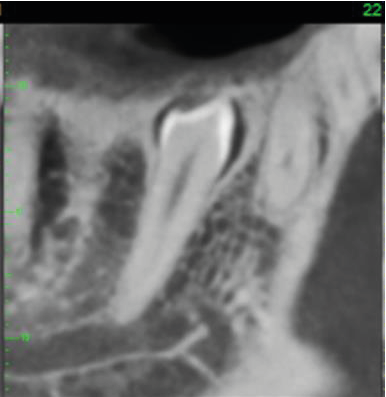

There is an unerupted supernumerary tooth lying in a mesioangular position, and with a lingual inclination, in the right premolar region of the mandible (image 2). It is 19.5mm in length.

2. The supernumerary tooth on mesio-lingual cross-section.